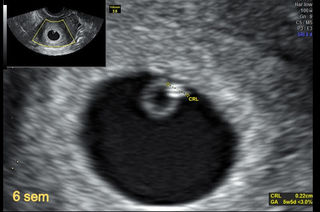

Ecografia 7 semanas que se ve. Tu mensaje me cae del cielo me ha pasado lo mismo hoy casualmente fui a la. Desde que supiste que estás embarazada seguramente tienes muchas ganas de saber si el sexo del bebé. Ya tengo 7 semanas se embarazo supuestamente y me hecho tres ecografias transvaginales y no se ve mi embrion por lo cual me siento triste el doctor tambien me dijo que no habia posibilidades de que el embarazo siga o prospere y me dijo que esperemos hasta 2 semanas mas.

Tienen forma de pequeñas esferas llenas de líquido que se hacen visibles en el espesor del endometrio E. Nesta 7ª semana de gravidez a flutuação de hormonas que está a acontecer no teu interior pode levar-te a estar mais sensível irascível ou irritável. El embrión sigue teniendo una cabeza muy grande en comparación con el resto del cuerpo pero en su interior el corazón ya se ha dividido en dos cámaras.

Desde las primeras semanas de embarazo esperamos que llegue el momento tan deseado de conocer si nuestro bebé será niño o niñaSin embargo esto sucederá alrededor de la semana 20 de embarazo en la que se realiza la ecografía clave para determinar el sexo del bebé. Normalmente las mujeres que se hacen una ecografía temprana en la semana 7 de embarazo son aquellas que vienen de un tratamiento de. Amanhã vou fazer uma ecografia mas como foi pedida pelo Medico de família só pode ser feita através da barriga.

La ecografía que se suele hacer en la semana 6 de embarazo es un ultrasonido transvaginal que permite ver la cámara gestacional. Eis o essencial sobre a 7ª semana de gestação. Nunca fiz uma eco pela barriga com tão pouco tempo de gestação. 7 Semanas de gestação. Ecografia 5 semanas. FÍjense al final q movÍa sus brazitos d. Con la ecografía podremos observar al embrión.